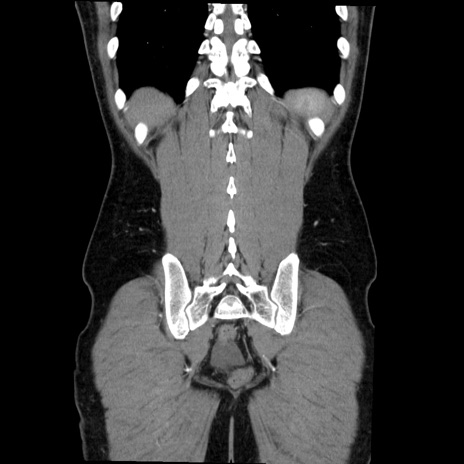

症例36(冠状断像)

【症例】20歳代 男性

【主訴】心窩部痛

【現病歴】今朝より上腹部痛あり。一旦軽快していたが再度出現したため救急要請。昨日夕に白身の魚を含む刺身を食べた。

【身体所見】BP 136/89mmHg、HR 74/min、BT 37.0℃、腹部:膨満、軟、心窩部に圧痛あり。反跳痛なし、筋性防御なし、腸雑音やや亢進あり。

【データ】WBC 17700、CRP 0.48